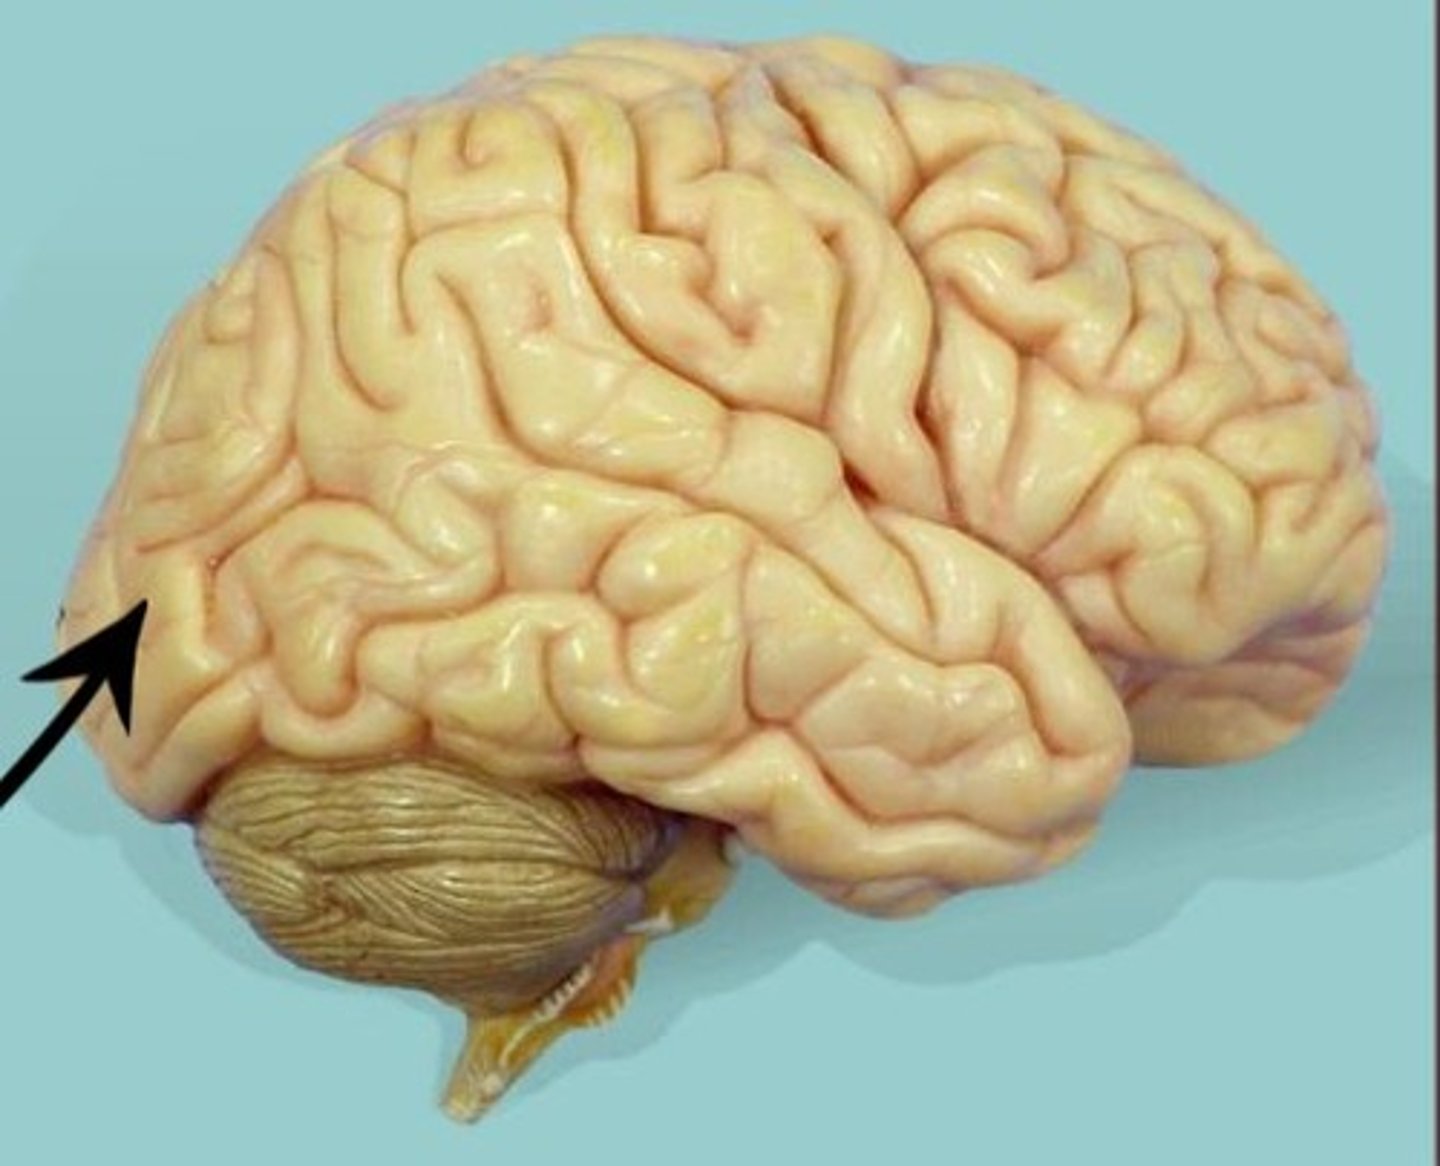

central sulcus

lateral sulcus

precentral gyrus

postcentral gyrus

frontal lobe

temporal lobe

parietal lobe

occipital lobe